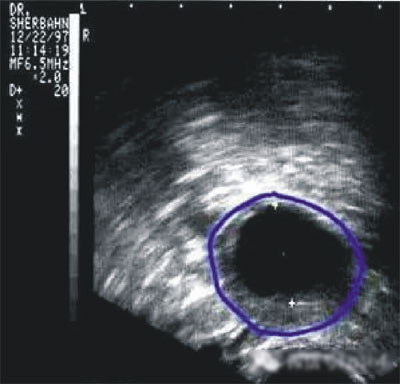

常用的監(jiān)測排卵方法有基礎(chǔ)體溫測定(BBT)、陰道B超監(jiān)測排卵、血清性激素測定等。

陰道B型超聲動態(tài)監(jiān)測卵泡的發(fā)育及排卵,是監(jiān)測排卵最準(zhǔn)確可靠的方法。通過陰道B超檢查可以了解子宮及雙側(cè)附件(卵巢和輸卵管)區(qū)的基本情況,測定卵巢內(nèi)的竇卵泡計數(shù),評估卵巢儲備功能,動態(tài)監(jiān)測排卵。